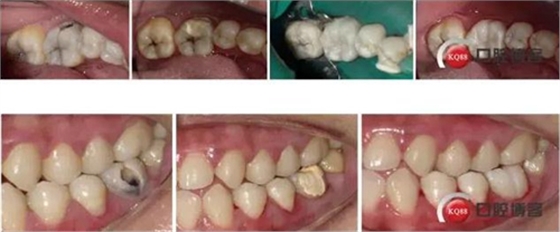

36頰側(cè)齲壞發(fā)黑,探診(+),叩診(-),冷刺激(++),松動(-),齦(-)

X-rays示36頰側(cè)齲壞達髓角,根尖周無明顯病變

治療:解釋病情,簽訂治療知情同意書,繳費,斯康杜尼+利多卡因局麻下上橡皮障,去腐,開髓,拔髓,10#K銼疏通根管,10#K銼測根長,MB:21mm;ML:21mm;DB:20.5mm;DL:21mm;NSK機擴馬達,21mmPLEX-V銼,扭力:3.5N.cm,轉(zhuǎn)速:400RPM。P0+EDTA敞開根管口(根管中上1/3),5.25%次氯酸鈉+生理鹽水交替沖洗,干燥,P1+EDTA疏通根管至根管全長,V1、V2+EDTA根管成型,DB,DL根尖1/3融合,5.25%次氯酸鈉沖洗后將次氯酸鈉存于根管內(nèi),蕩洗機關(guān)水蕩洗20S/根管,蒸餾水蕩洗20S/根管,干燥,隔濕,AHplus糊劑+2506牙膠尖次氯酸鈉消毒后酒精棉球拭干后垂直加壓充填,置小棉球,暫封膏+聚羧酸鋅水門汀暫封。去除橡皮障,拍片。

處理:去除暫封物,上橡皮障,HE面去腐,備洞,富士2墊底,酸蝕,干燥,涂布粘結(jié)劑,光照,流體樹脂襯洞,美塑樹脂充填,下橡皮障,調(diào)合,打磨,拋光

1、對于頰側(cè)齲壞的后牙,有事可以就齲開髓,沒必要直接he面開髓,這樣可以保留更多的牙體組織